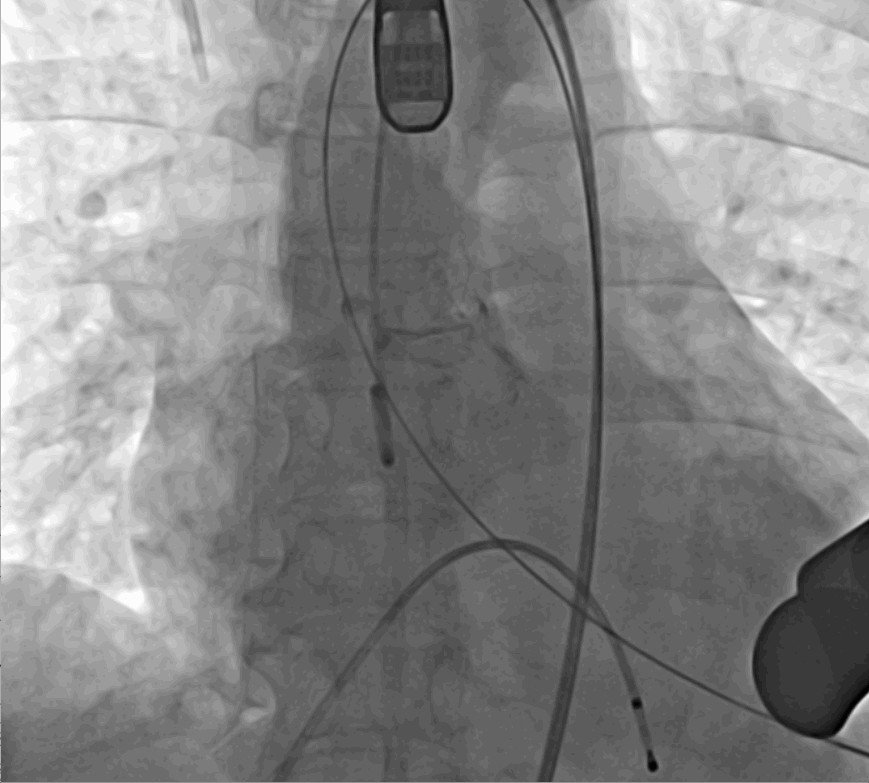

術(shù)前DSA影像圖

手術(shù)采用經(jīng)心尖入路,對(duì)患者進(jìn)行全麻后,在左側(cè)心尖處做3-4cm微創(chuàng)手術(shù)切口,在DSA及超聲引導(dǎo)下手術(shù)順利完成。從導(dǎo)入器械到完成瓣膜置入,僅耗時(shí)約10分鐘。術(shù)后即刻主動(dòng)脈瓣返流程度由術(shù)前大量返流轉(zhuǎn)為消失,患者于導(dǎo)管室拔除氣管插管,次日由ICU轉(zhuǎn)入普通病房。